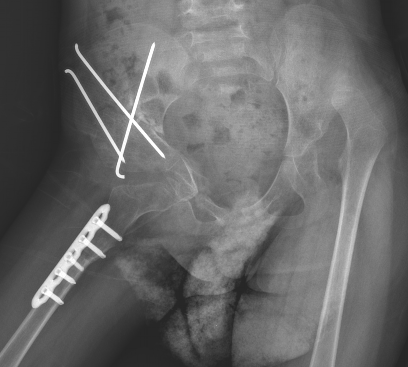

案例痛心,3歲才發(fā)現(xiàn),需多處截骨手術(shù)。???來自信宜市丁堡鎮(zhèn)的小姑娘,3歲多就診才發(fā)現(xiàn)患者雙側(cè)DDH,圖為右側(cè)進(jìn)行三聯(lián)截骨手術(shù)治療后,左側(cè)需擇期再手術(shù)治療。DDH科普小知識(shí)一、越早治療效果越好,應(yīng)早至滿月嬰兒。二、①看臀紋,②蛙式試驗(yàn),③下肢短縮試驗(yàn)。①看臀紋(要對(duì)稱),指大腿與臀部鏈接的紋理,不對(duì)稱要就診,請(qǐng)注意不對(duì)稱并非意味著一定是患有DDH。②蛙式試驗(yàn)(像小青蛙一樣做動(dòng)作),寶寶雙側(cè)髖、膝關(guān)節(jié)屈曲90°后外展,正常新生兒及嬰兒可外展80°左右。(圖示右側(cè)為患側(cè),圖片源自網(wǎng)絡(luò))③下肢短縮試驗(yàn),寶寶雙側(cè)髖、膝關(guān)節(jié)屈曲,足跟平放于床面上,正常兩側(cè)膝頂點(diǎn)等高。(圖示右側(cè)為患側(cè),圖片源自網(wǎng)絡(luò))三、科學(xué)就醫(yī):6月齡內(nèi)查B超,半歲后查正蛙位髖關(guān)節(jié)X線片。1.小于6月齡的寶寶因髖臼和股骨頭主要為軟骨,x線平片不能顯示,超聲可做形態(tài)學(xué)評(píng)估,常用Graf法篩查髖關(guān)節(jié)形態(tài)異常。髖關(guān)節(jié)發(fā)育不良(DDH)X線檢查病情程度分類(圖片源自網(wǎng)絡(luò))2.髖關(guān)節(jié)發(fā)育不良(DDH)股骨頭近端骨化中心出現(xiàn)(4~6月齡),即可拍前后位片、髖外展位和內(nèi)旋位片,常用骨盆正位及蛙位X線片評(píng)估。